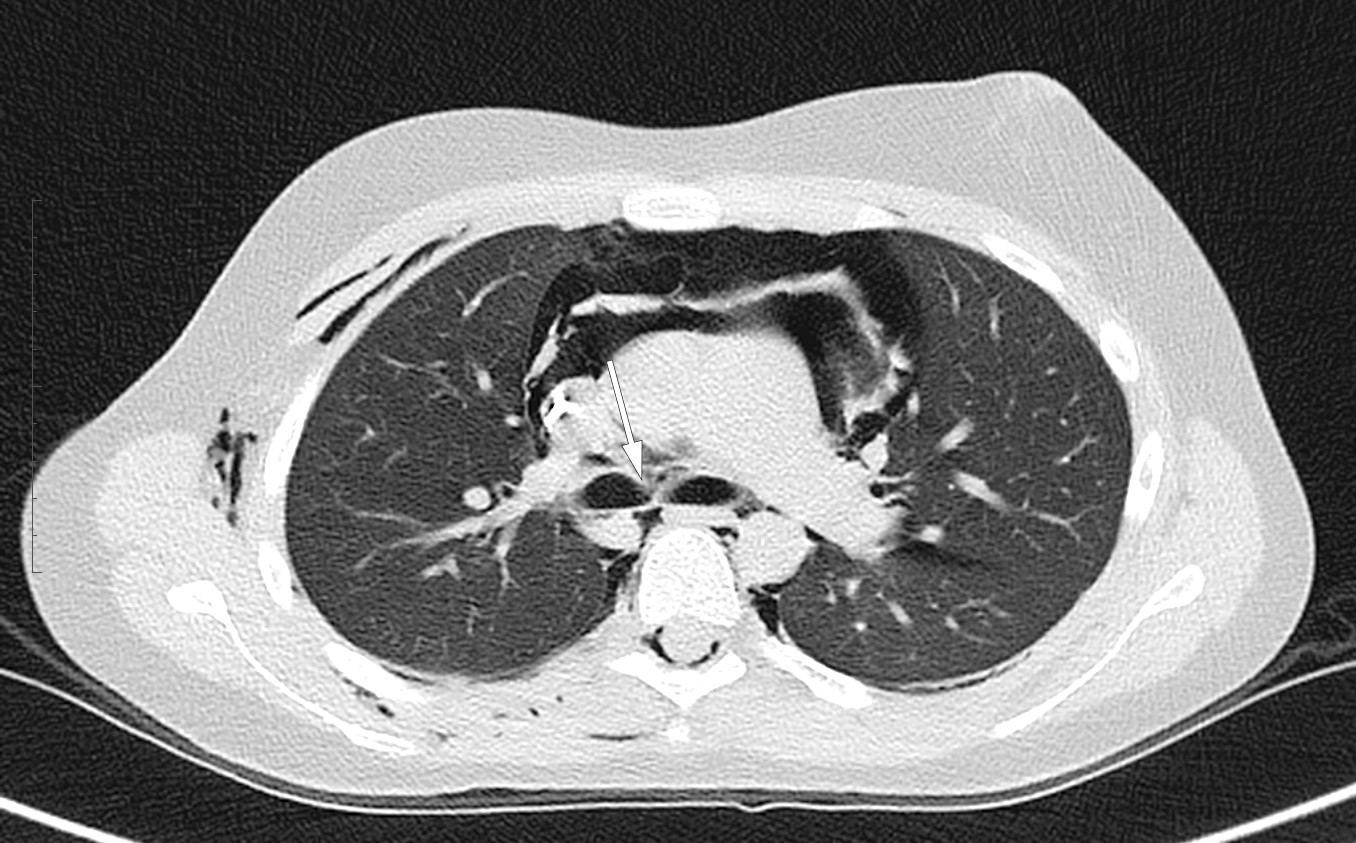

Tre timer etter ankomst var acidosen i bedring. Respirasjonen var mindre forsert, og pasienten virket ikke lenger forvirret. Han klaget over smerter midt i brystet, var nakkestiv og klarte ikke å bøye haken ned mot brystet, men hadde ikke hodepine. Hevelsen i ansikt hadde gått noe tilbake, og han klarte nå å åpne høyre øye. Det ble tatt CT thorax (figur 2), som bekreftet pneumomediastinum, bløtvevsemfysem og luft rundt begge lunger, men ikke kollapset lunge som ved pneumothorax. Ved regranskning så man en mulig rift ved høyre hovedbronkus' avgang helt inne ved carina. Det var ingen fri væske i mediastinum. Det var ekstradural luft i spinalkanalen i hele torakalsegmentet og undersøkte cervikalavsnitt.